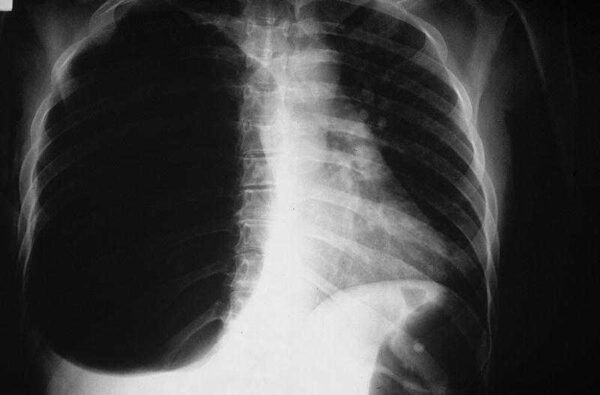

El neumotórax es una condición médica que ocurre cuando se acumula aire en el espacio entre el pulmón y la pared torácica, lo que provoca una pérdida de presión que puede colapsar parcial o completamente el pulmón afectado. El inicio del neumotórax suele ser agudo y puede estar asociado con síntomas característicos, como dolor pleurítico y disnea.

Neumotórax espontáneo: El neumotórax espontáneo ocurre sin una causa externa obvia, y suele manifestarse en pacientes jóvenes, especialmente aquellos que son altos y delgados. En estos casos, la condición puede estar relacionada con la presencia de vesículas o bullas, que son áreas de aire atrapadas en los pulmones. Estas vesículas o bullas pueden romperse espontáneamente, liberando aire en el espacio pleural y provocando un colapso pulmonar. Los pacientes con neumotórax espontáneo suelen no tener antecedentes de trauma torácico o enfermedades pulmonares significativas.

Neumotórax secundario: En algunos casos, el neumotórax puede ser secundario a enfermedades pulmonares subyacentes o a factores que aumentan el riesgo de que se presente esta condición. Por ejemplo, las personas con enfermedades pulmonares obstructivas crónicas, como la enfermedad pulmonar obstructiva crónica (EPOC), o aquellas que tienen antecedentes de enfermedades pulmonares, como la tuberculosis, tienen un mayor riesgo de desarrollar neumotórax secundario debido a la fragilidad del tejido pulmonar. En estas situaciones, el neumotórax puede ser el resultado de una ruptura en el tejido pulmonar debilitado.